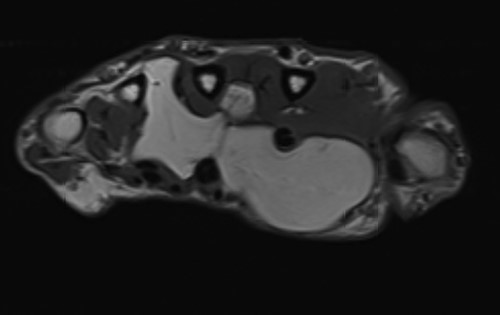

The patient underwent nerve conduction studies, which suggested a carpal tunnel lesion on the left. Magnetic resonance imaging (MRI) of the left hand confirmed the presence of a large, lobulated and well-defined fatty lesion in the palm centred between the flexor tendons and metacarpals, with dorsal and volar extensions (Fig. 1), and a proximal component within the carpal tunnel causing median nerve compression (Fig. 2). The investigations were discussed at the regional sarcoma multidisciplinary team meeting and findings were suggestive of a benign lipoma.

Axial MRI view demonstrating volar and dorsal extension of the fatty lesion from the middle of the palm.